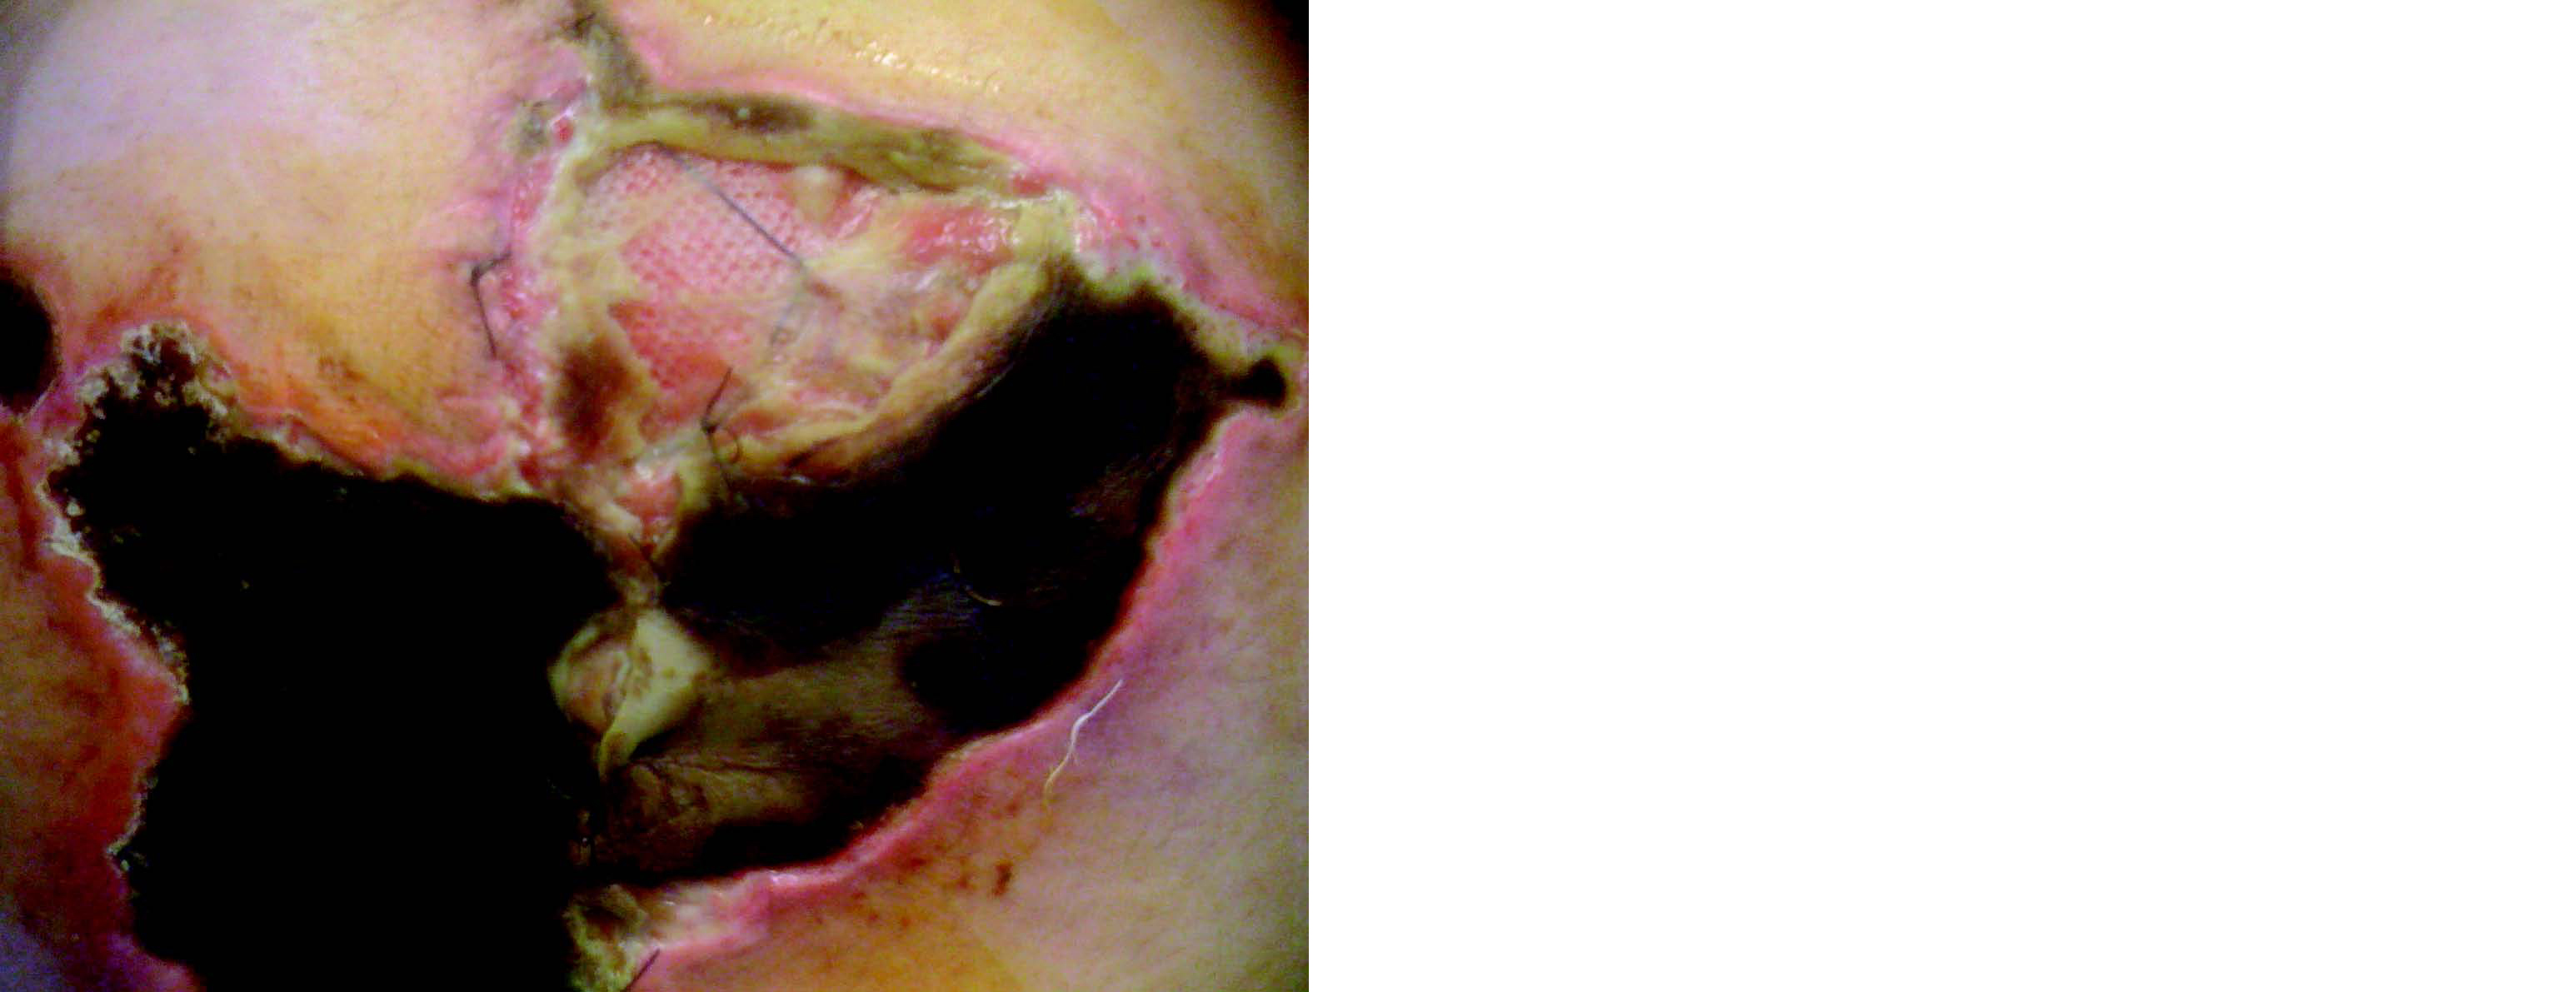

Une étude rétrospective Grenobloise publiée en 201912 a rapporté un taux de succès 95 % en termes de fermeture pariétale sur les 162 patients inclus. Cependant, des complications ont été observées chez plus de 50 % des patients, parmi lesquelles les séromes, hématomes, abcès et nécroses cutanées étaient les plus fréquentes. Les complications majeures (classification de Clavien-Dindo ≥ III) étaient limitées à 16 %, avec une mortalité globale de 3 %, principalement liée à des complications respiratoires ou cardiovasculaires. Ces résultats confirment la faisabilité et l'efficacité de cette technique, en particulier chez des patients présentant des comorbidités importantes (obésité, insuffisance respiratoire chronique). En effet, 50 % présentaient une insuffisance respiratoire chronique et un score ASA de III. Un tiers des patients étaient obèses, avec un IMC moyen de 33 kg/m². Ces résultats sont en accord avec d'autres études de cohortes similaires13, 14.

Figure 8 Nécrose cutanée après cure d'éventration géante selon Goni-Moreno

La technique de Goni Moreno est une solution précieuse pour la gestion des éventrations géantes avec perte de droit de cité, notamment en permettant une fermeture pariétale sans tension de manière efficace. Cependant, elle n'est pas sans risques. Les complications associées, telles que les séromes, hématomes, et nécroses cutanées, nécessitent une surveillance post-opératoire attentive.